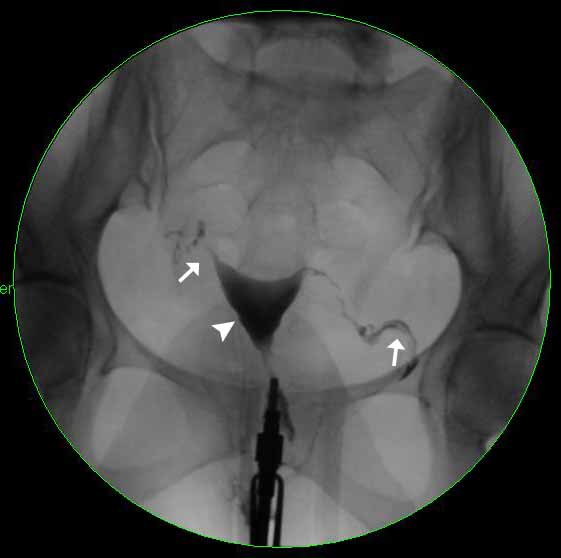

Peritubal adhesions on hysterosalpingogram Image What Is Fluoroscopy Hysterosalpingogram By injecting a contrast dye into the uterus,. A hysterosalpingogram is a diagnostic imaging modality primarily utilized in assessing female infertility. A hysterosalpingogram (hsg) is a fluoroscopic examination of the uterus and the fallopian tubes, most commonly used in the investigation of infertility or. In this procedure, a provider uses fluoroscopy to provide images of biologically female reproductive organs. What Is Fluoroscopy Hysterosalpingogram.

Venous intravasation on hysterosalpingogram Radiology Case What Is Fluoroscopy Hysterosalpingogram In this procedure, a provider uses fluoroscopy to provide images of biologically female reproductive organs. By injecting a contrast dye into the uterus,. A hysterosalpingogram (hsg) is a fluoroscopic examination of the uterus and the fallopian tubes, most commonly used in the investigation of infertility or. A hysterosalpingogram is a diagnostic imaging modality primarily utilized in assessing female infertility. What Is Fluoroscopy Hysterosalpingogram.